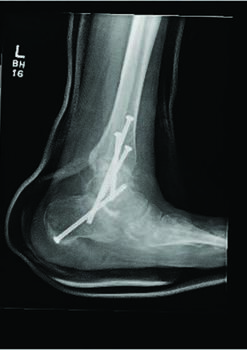

There are several studied and suggested surgical fixation options for treating complicated diabetic ankle fractures. As mentioned earlier, inappropriate treatment of these injuries can often lead to complications including the worst case scenario of Charcot arthropathy, and potential resultant limb loss. Hence, the common fundamental goals currently used for Charcot reconstruction also apply in ankle fracture fixation for patients with complicated diabetes.7 Specifically, these include obtaining a fixation construct with maximum rigidity and absolute stability, extending the fixation beyond the immediate zone of injury and planning incisions to minimize soft tissue trauma and optimize healing.4 Some fixation constructs suggested in recent literature include: circular external frame fixation; internal fixation using screws and plates; tibiotalocalcaneal (TTC) nail construct; and even locked fibular intramedullary nail fixation.4,8-10

Facaros and colleagues presented a case report of a patient with diabetes and neuropathy who sustained a displaced fibular fracture with significant joint subluxation and syndesmotic injury.11 Subsequent surgical intervention consisted of ORIF with plate fixation, multiple pro-syndesmotic screws and application of a multiplanar circular external fixator. This allowed a maximally stable and rigid construct and also allowed the patient to fully weight bear postoperatively on the external fixator. The patient underwent removal of the external fixator after 12 weeks without any long-term sequelae.11The use of multiple syndesmotic screws regardless of a syndesmotic injury is repeatedly suggested in the literature, as it allows for a more mechanically stable construct.4